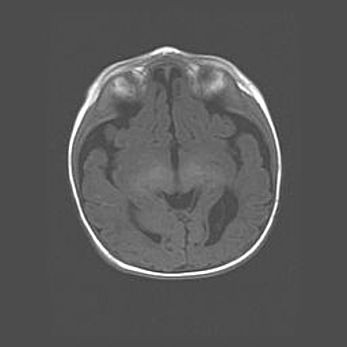

Лейкомаляция с кистозно-глиозной дегенерацией головного мозга.

Возраст: 2 месяца 25 дней

Вес: 6400 г

Окружность головы: 40 см

Срок гестации: 41 неделя

Лейкомаляцию относят к ишемически-гипоксическим повреждениям головного мозга, диагностируемым у новорожденных. При лейкомаляции в головном мозге обнаруживают очаги некроза, возникшие после тяжелой гипоксии и нарушения кровотока. В процессе морфогенеза очаги проходят три стадии: 1) развития некроза, 2) резорбции и 3) формирования глиозного рубца или кисты. Перивентрикулярная лейкомаляция (ПЛ) встречается примерно в 12% случаев среди новорожденных, обычно – у недоношенных детей, причем, частота ее зависит от массы, с которой младенец появился на свет. Наибольшее число малышей страдает лейкомаляцией, если масса при рождении 1500-2500 г.